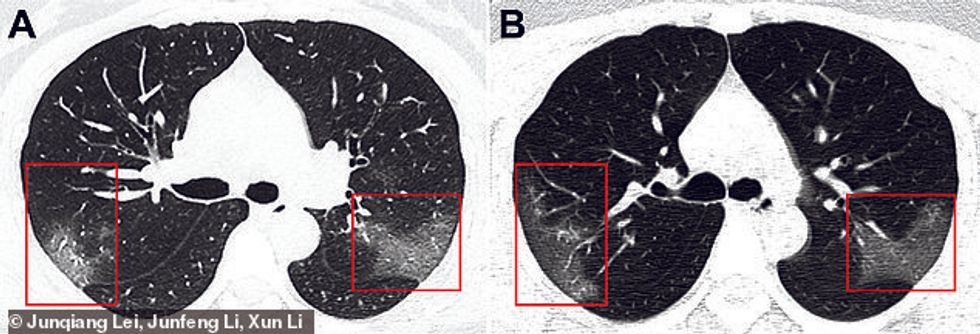

Në imazhe mjekët kanë hasur në hije të bardha të njohura si xhamat e qumështit, që paralajmërojnë se mushkëritë pjesërisht janë të mbushura me lëngje.

Imazhet janë publikuar në revistën shkencorë Radiology, kurse tekstin e kanë përpiluar ekipi i mjekëve të spitalit në Landzou. Ata pretendojnë se pacientët e infektuar me coronavirus, fillimisht vërejtën se kanë infeksione që mund të dëmtojnë mushkëritë dhe të shkaktojnë ndezjen e tyre që kërcënon jetën e njeriut.

Sipas tyre mushkëritë mbushen me lëngje, dhe për këtë arsye mjekët menjëherë u japin terapinë që u ndihmon në hapjen e kanaleve të frymëmarrjes.

Mjekët paralajmërojnë së në fillim shumë lehtë mund të ngatërrohet coronavirusi me ndezjen e mushkërive. Megjithatë imazhet e rëntgenografisë kanë treguar se pas tre ditëve gjendja e pacientit përkeqësohet siç ka ndodhur në raste me SARS dhe MERS, viruse këto gjithashtu që kishin shpërthyer në Kinë. /Telegrafi/